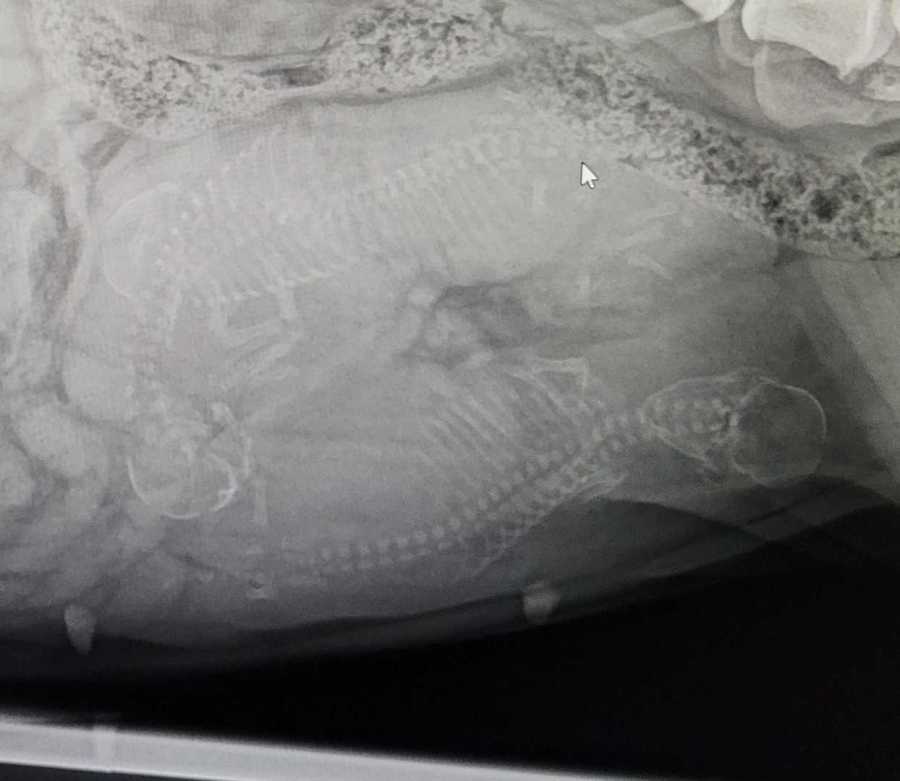

Am Dienstag, den 11.4.23 um ca. 20 Uhr wurde der H- Wurf per Kaiserschnitt zur Welt gebracht.

Wir sind dankbar für euch 3 Wunder, den es sah nicht mehr danach aus das einer Überlebt hat, aber es haben tatsächlich alle 3 Überlebt.

Wir waren gerade zur Kontrolle in der Tierklinik Wodecki, Mama und den Baby geht es gut.